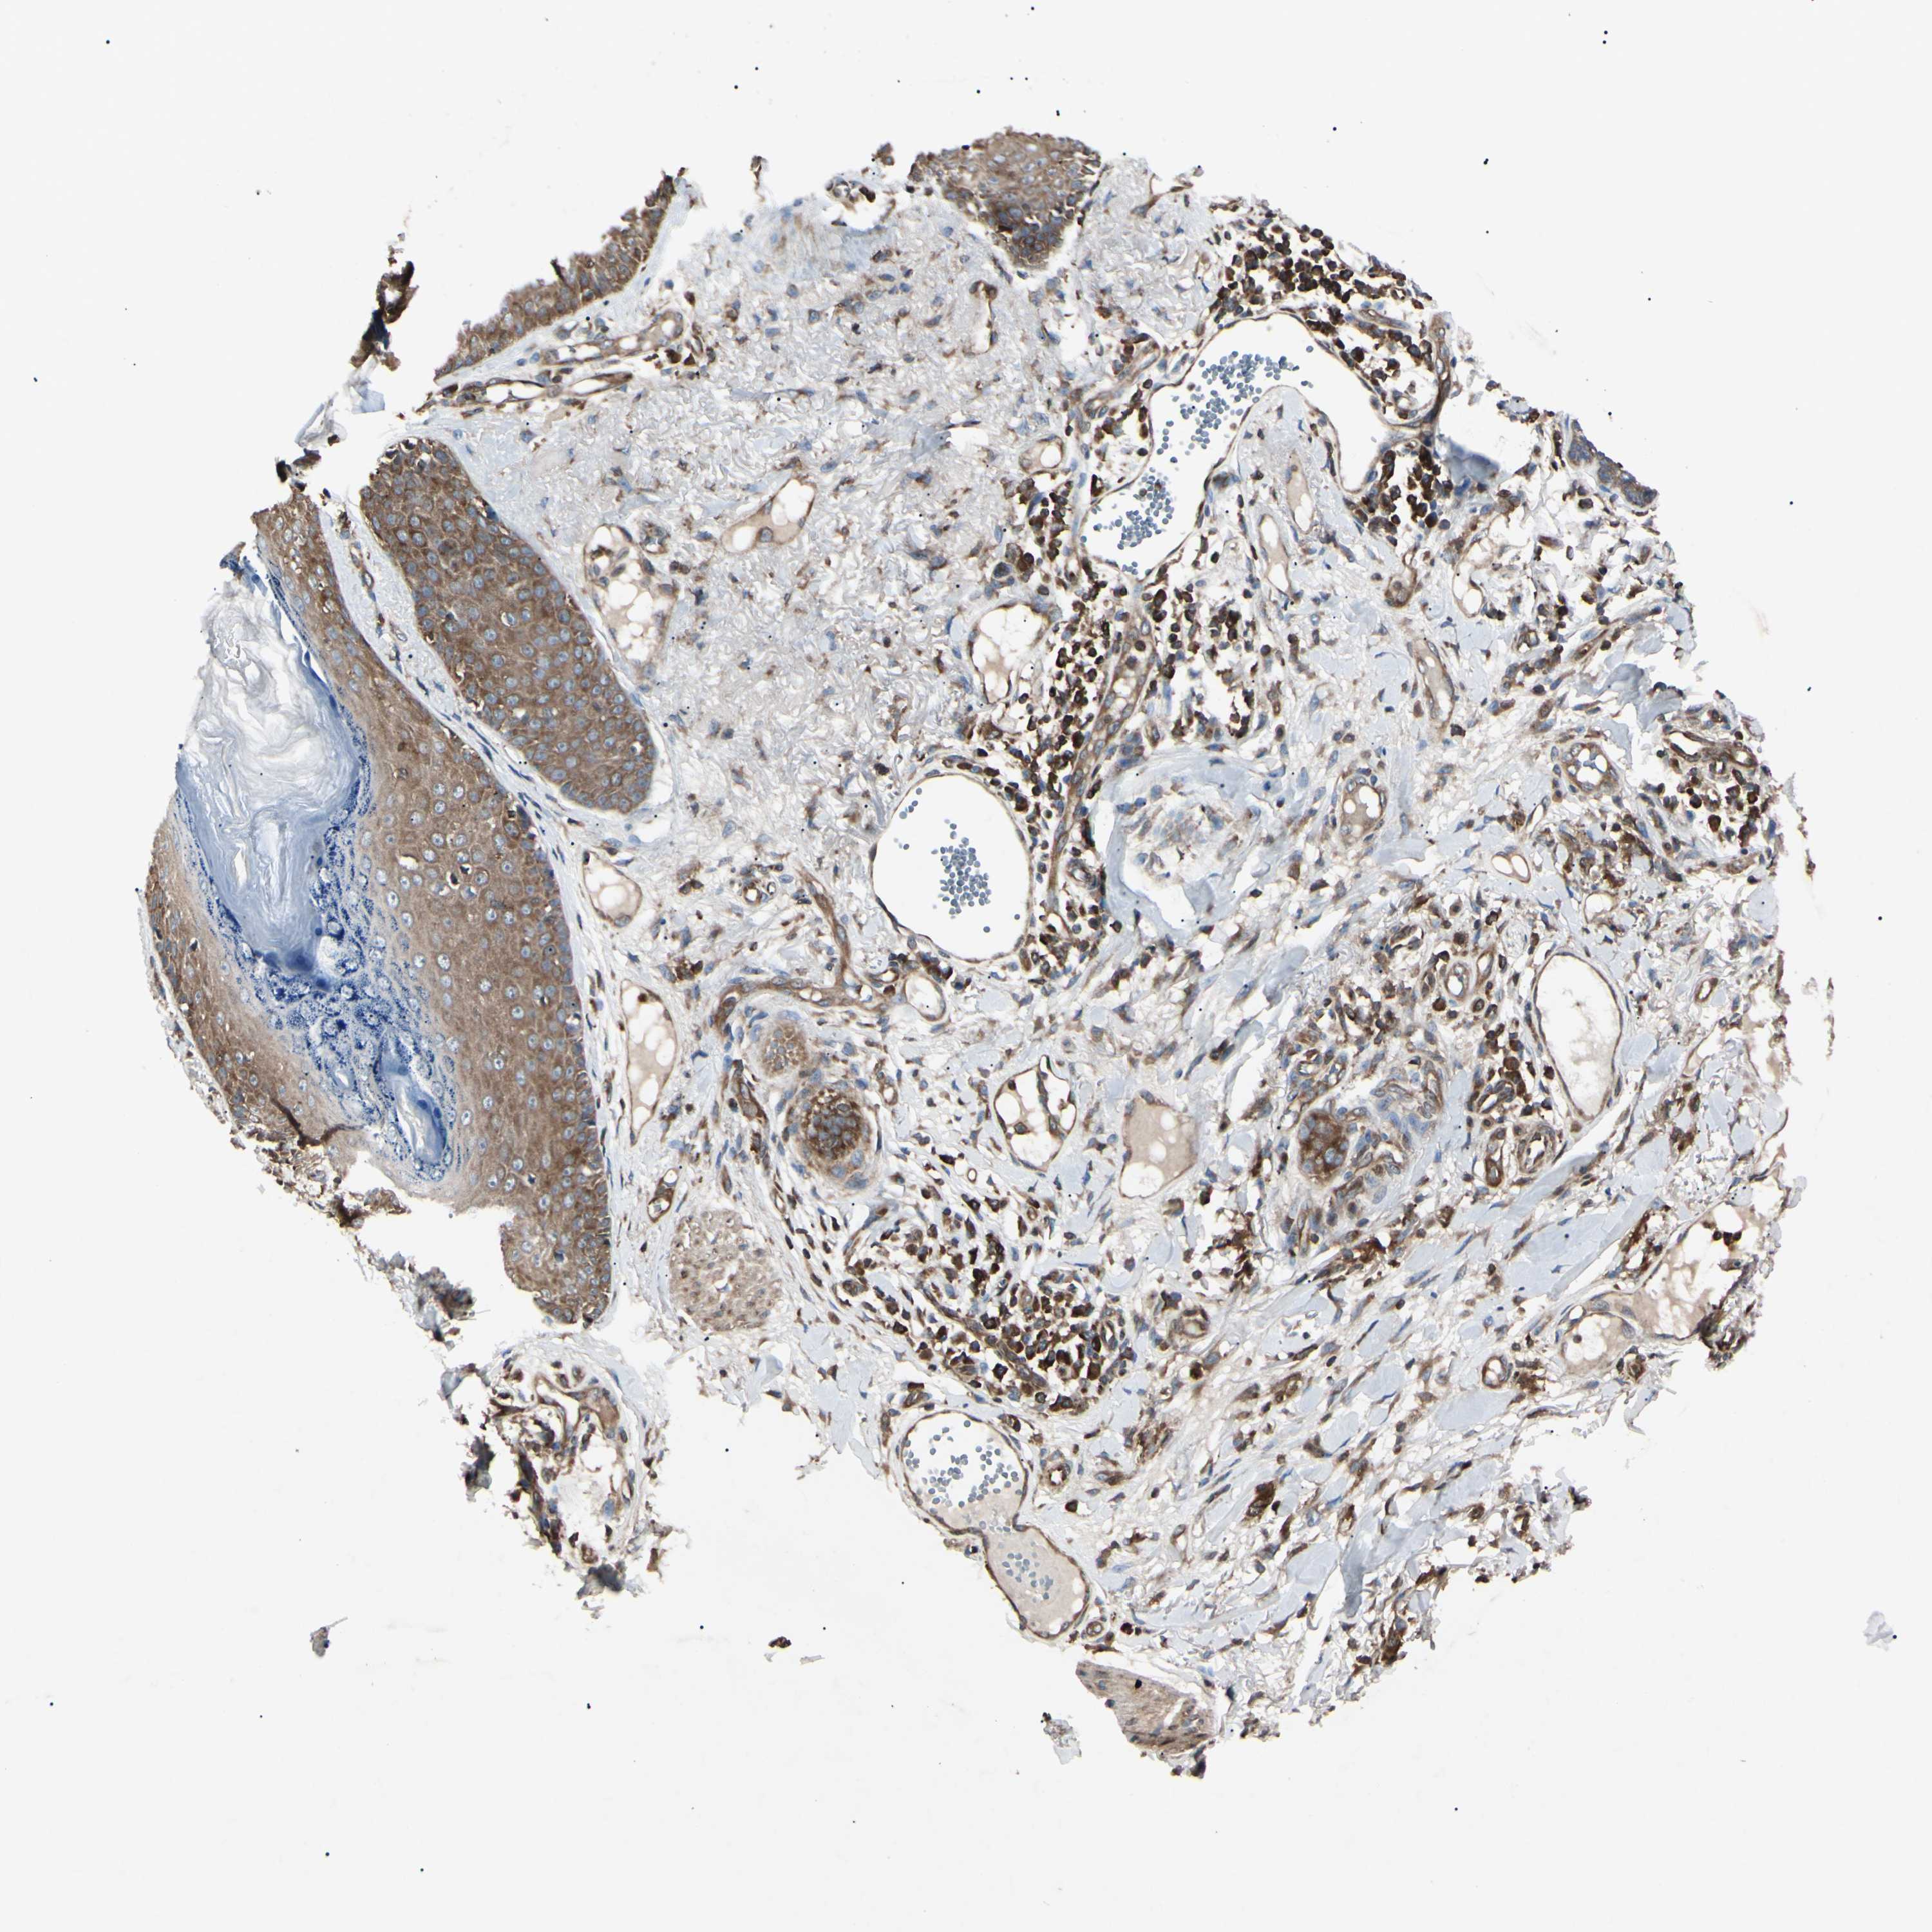

Basal cell and squamous cell cancer

SKIN CANCER - Protein expressioni

A mouse-over function shows sample information and annotation data. Click on an image to view it in a full screen mode. Samples can be filtered based on level of antibody staining by selecting one or several of the following categories: high, medium, low and not detected. The assay and annotation is described here.

Antibody stainingi

Antibody staining in the annotated cell types in the current human tissue is reported as not detected, low, medium, or high, based on conventional immunohistochemistry profiling in selected tissues. This score is based on the combination of the staining intensity and fraction of stained cells.

Each image is clickable and will lead to virtual microscopy that enables deeper exploration of all samples and also displays staining intensity scores, fraction scores and subcellular localization as well as patient and tissue information for each sample.

Antibody CAB009337

Staining

High

Intensity

Quantity

Location

Squamous cell carcinoma, NOS